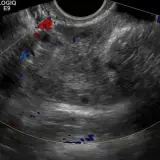

PACSで期待されるツールを完備した完全インタラクティブな症例 — スクロール、ウィンドウ調整、ズーム、パン、計測、ROI、フルスクリーンモード。

重要な所見を症例画像上に直接ハイライトする豊富なアノテーション。症例解説内のリンクされた所見をクリックすると、スキャン上の正確な位置へジャンプできます。

アノテーション付きの画像所見とイラストで効率的に学習